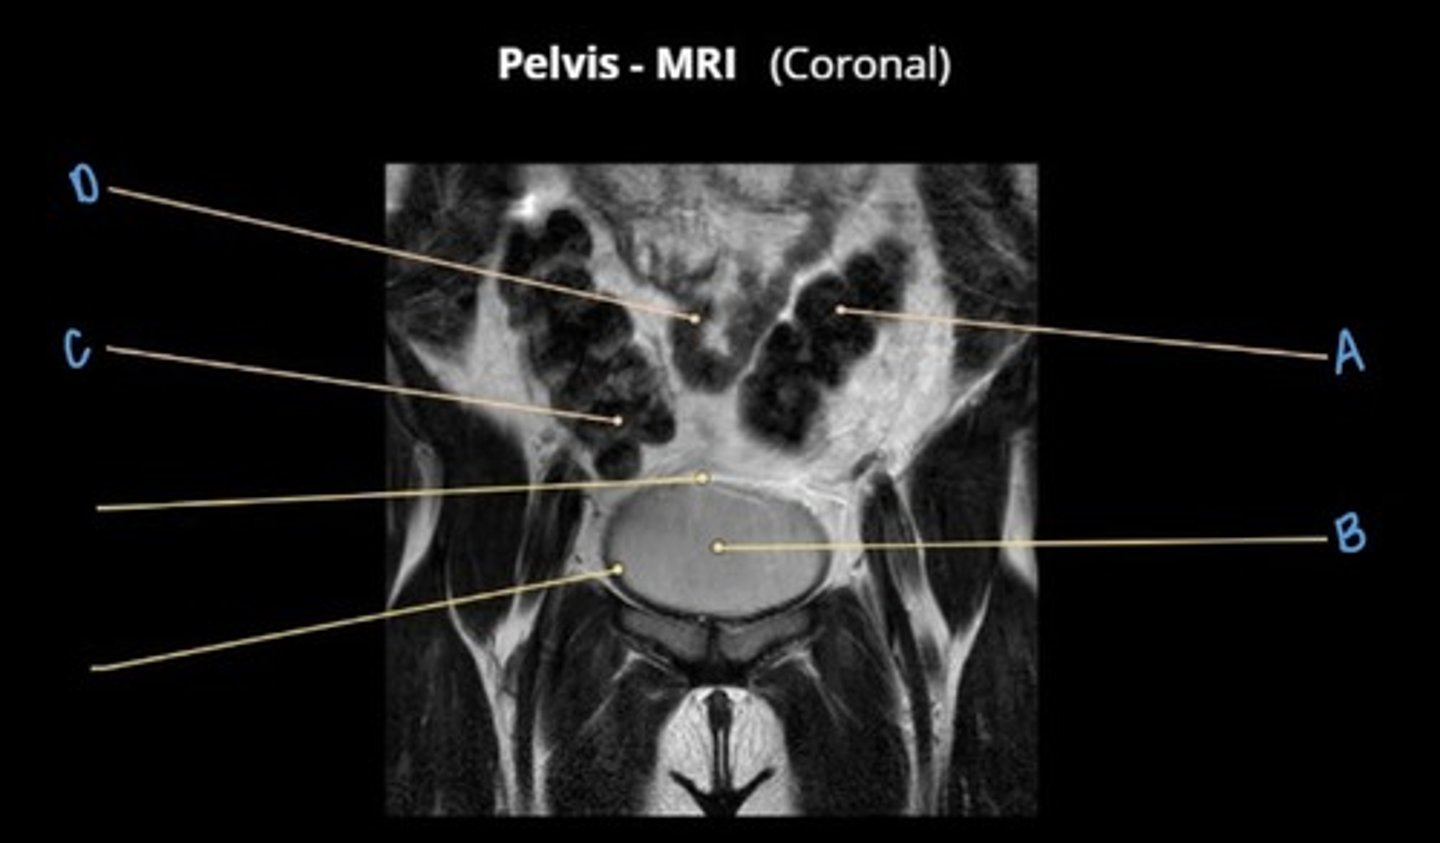

A

obturator internus muscle

B

levator ani muscle (pubic diaphragm)

C

gluteus maximus muscle

D

pubic symphysis

E

rectus abdominus muscle

bladder

prostate

F